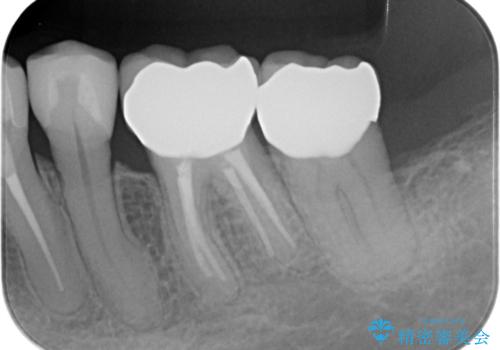

銀歯を除去したのち、虫歯を丁寧に除去し、歯を残せるのかどうかをしっかりと評価し、長期的な予後を見据えた虫歯治療を行っていきます。

銀歯の下で虫歯が再発していた歯は、無理に残しても割れてしまう可能性が非常に高いと考えたため、相談の上抜去を行いインプラント治療を行っていくこととしました。